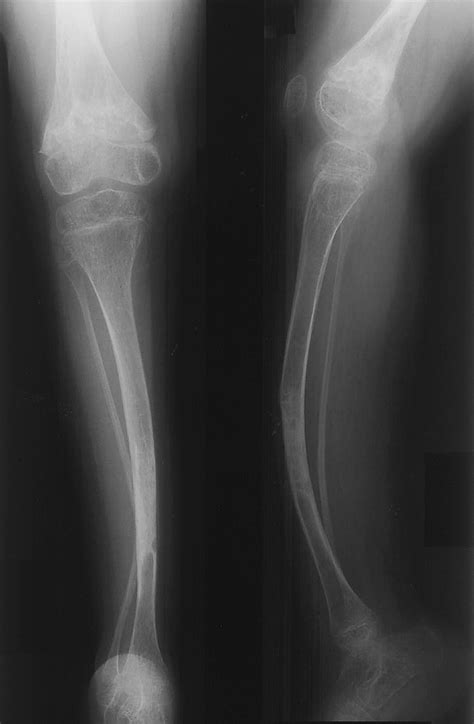

Osteogenesis Imperfecta (OI), commonly known as brittle bone disease, is a genetic disorder characterized by bones that break easily, often from little or no apparent cause. This condition affects both children and adults, significantly impacting their quality of life. One of the key treatments for managing Osteogenesis Imperfecta is the use of bisphosphonates, a class of drugs that help to strengthen bones and reduce the frequency of fractures. This blog post delves into the intricacies of Osteogenesis Imperfecta Bisphosphonate treatment, its benefits, potential side effects, and the latest research findings.

Osteogenesis Imperfecta is caused by a defect in the gene that produces type I collagen, a protein essential for building bones. There are several types of OI, ranging from mild to severe, each with varying symptoms and levels of bone fragility. The most common symptoms include:

• Bone deformities